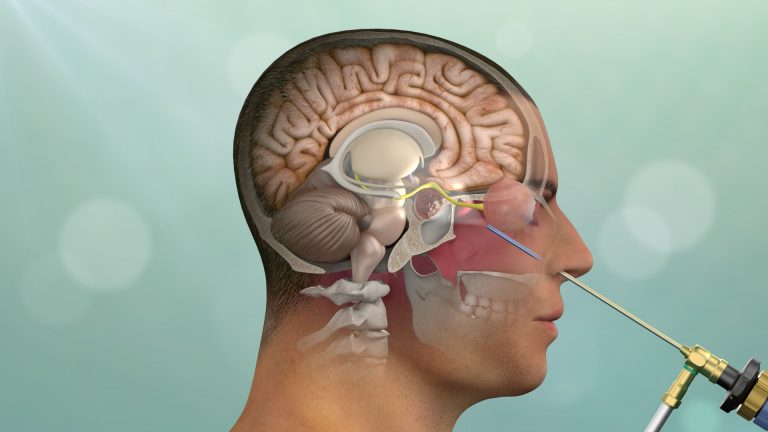

یکی از غدههای مهم بدن غده هیپوفیز است که در قاعده جمجمه و در عمق مغز قرار دارد که ممکن است دچار رشد غیرطبیعی شود. این بیماری جز تومورهای مغزی میباشد. این غده با همکاری غده هیپوتالاموس فعالیتهای مختلفی را انجام میدهد که دو نمونه از این فعالیتها شامل...